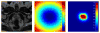

This paper proposes a method for segmenting the prostate on magnetic resonance (MR) images. A superpixel-based 3D graph cut algorithm is proposed to obtain the prostate surface. Instead of pixels, superpixels are considered as the basic processing units to construct a 3D superpixel-based graph. The superpixels are labeled as the prostate or background by minimizing an energy function using graph cut based on the 3D superpixel-based graph. To construct the energy function, we proposed a superpixel-based shape data term, an appearance data term, and two superpixel-based smoothness terms. The proposed superpixel-based terms provide the effectiveness and robustness for the segmentation of the prostate. The segmentation result of graph cuts is used as an initialization of a 3D active contour model to overcome the drawback of the graph cut. The result of 3D active contour model is then used to update the shape model and appearance model of the graph cut. Iterations of the 3D graph cut and 3D active contour model have the ability to jump out of local minima and obtain a smooth prostate surface. On our 43 MR volumes, the proposed method yields a mean Dice ratio of 89.3 ±1.9%. On PROMISE12 test data set, our method was ranked at the second place; the mean Dice ratio and standard deviation is 87.0±3.2%. The experimental results show that the proposed method outperforms several state-of-the-art prostate MRI segmentation methods.